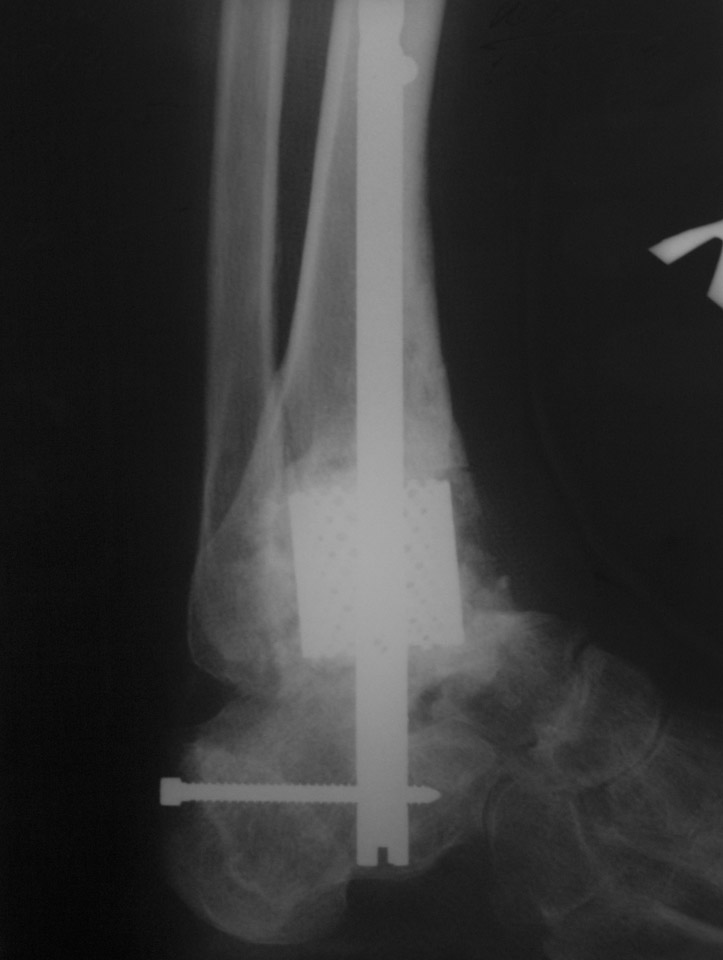

Сегодня пациентке снята иммобилизирующая повязка, выполнен

рентгенконтроль. Рекомендована ходьба с полной нагрузкой в

ортопедической обуви. Следующий контрольный осмотр, если ничего

больную беспокоить не будет, планируем месяцев через 6.